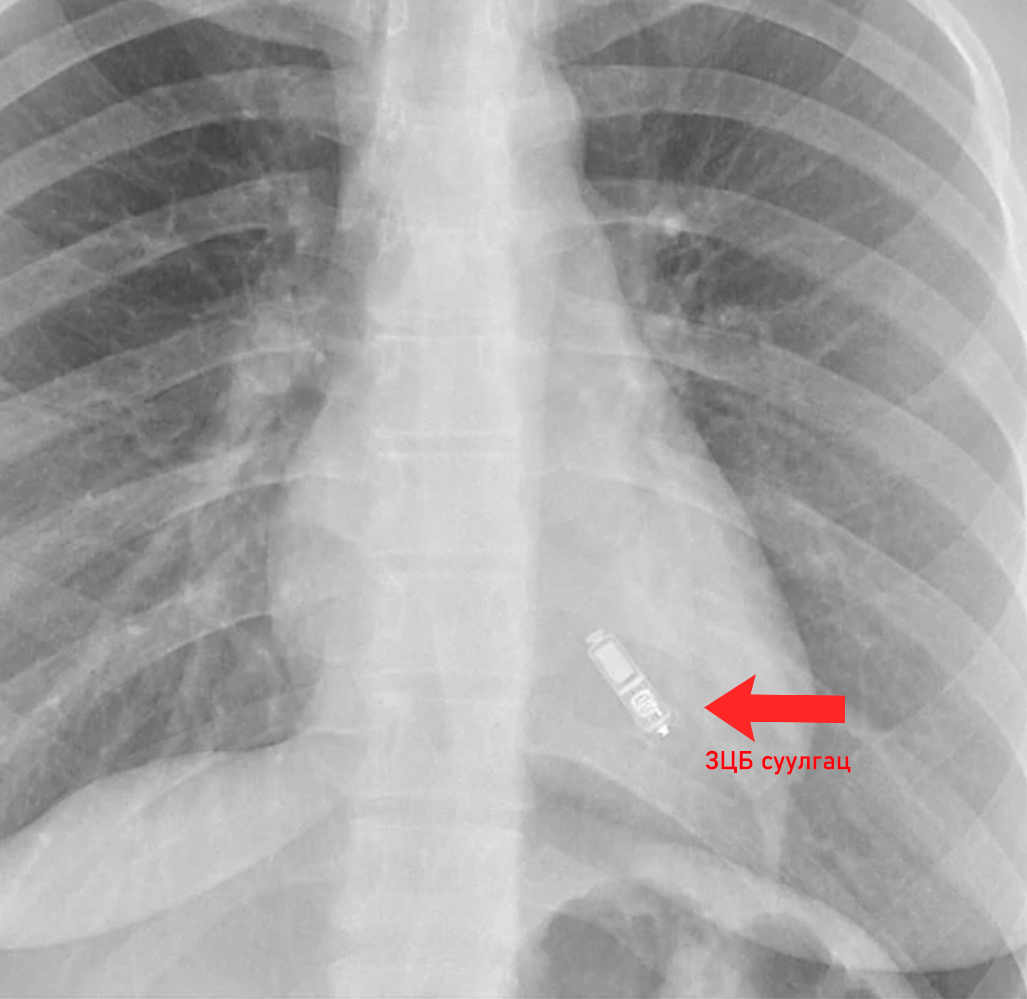

Урт хугацааны зүрхний цахилгаан бичлэгийн хяналтын суулгац гэдэг нь хүний зүрхэнд үүсэж буй аюултай хэм алдагдлуудыг 2-3 жилийн хугацаанд бүртгэн авах боломжтой, жижиг хэмжээний суулгац бөгөөд уг суулгацыг биеийн цээжний өмнөд хэсэгт хэсэг газрын мэдээ алдуулалт дор жижиг (~0.5см) зүслэг хийн, арьсанд тарих маягаар суулгадаг.

Улсын гуравдугаар төв эмнэлэг оношилгооны энэхүү технологийг энэ оны нэгдүгээр сард шинээр нээгдсэн Зүрхний хэм судлалын төвийн эмнэлзүйн тусламж үйлчилгээнд ашиглах юм.